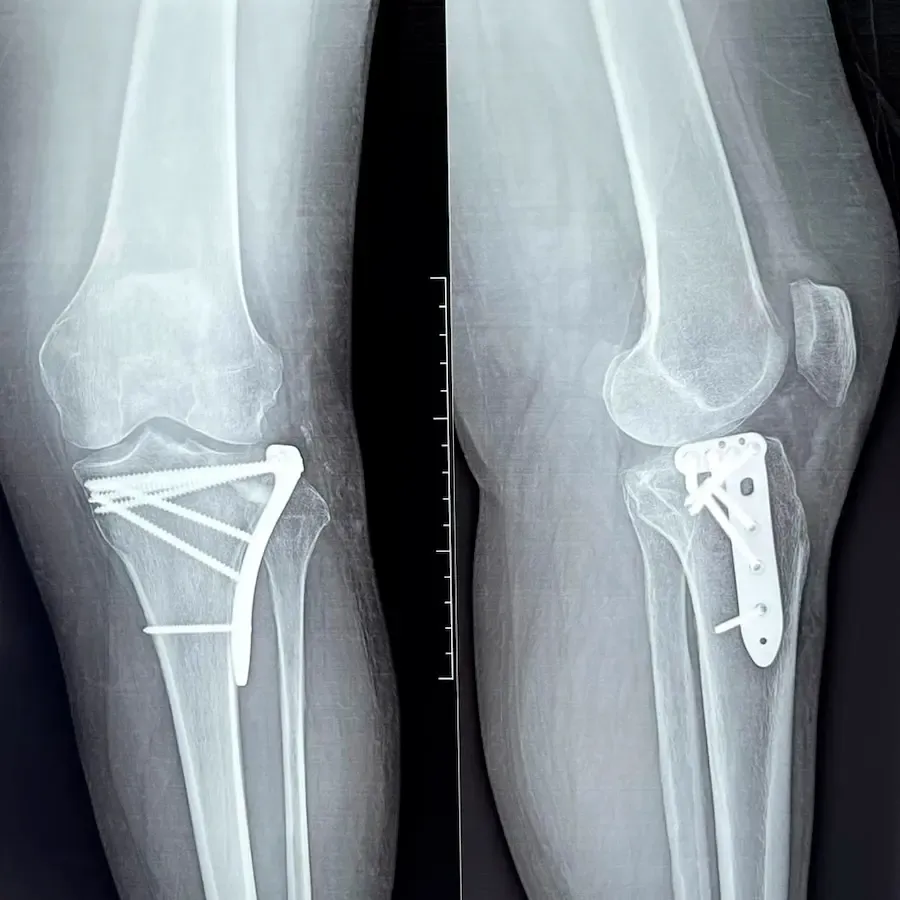

Osteotomía tibial o femoral

Osteotomía tibial o femoral por deformidad en pacientes jóvenes

Descripción: Corte del hueso para corregir el eje de carga de la pierna.

Indicado para:

• Artrosis localizada en pacientes jóvenes.